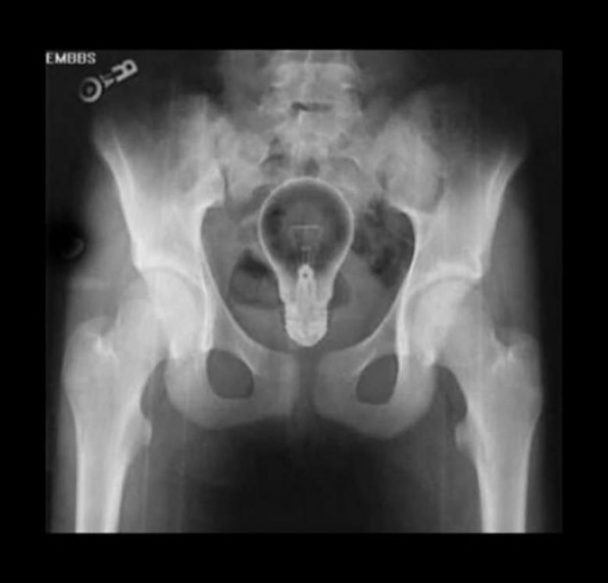

Röntgen filmlerinden "akıl almaz şeyler

Hastane koridorlarına düşenler bilir… Doktora görün, tahlilleri yaptır, röntgenleri çektir falan filan derken sayılmadan ömür gider. Gelin ki bu sefer ilginç şeyler çıkmış ki görün ağzımız açık kaldı…